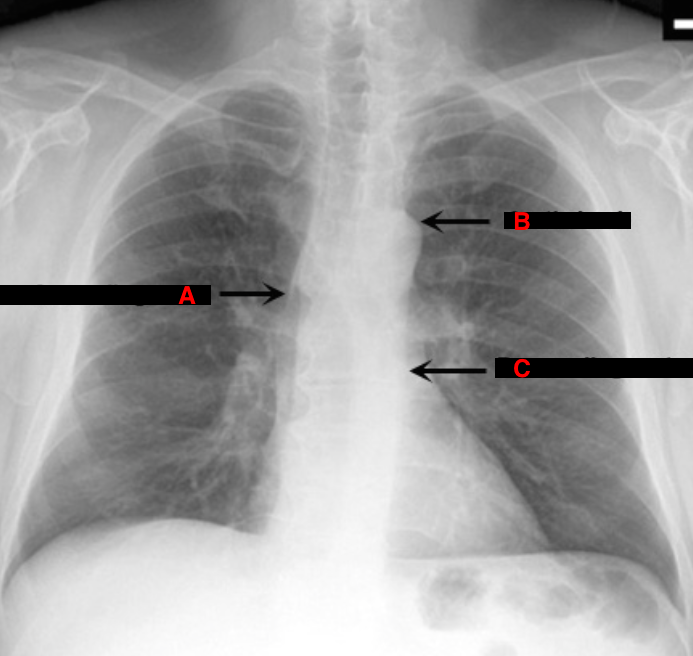

What are the 3 possible areas for mediastinal widening?

Identify A, B and C

A. Ascending aorta

B. Aortic knob

C. Descending aorta